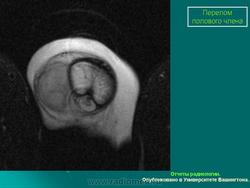

Травма. Ср, 19/10/2011 - 23:43 #1 Катенёв Валенти... Не на сайте Был на сайте: 7 лет 5 месяцев назад Зарегистрирован: 22.03.2008 - 22:15 Публикации: 54876 Травма мочеточника.Приложения: Вс, 25/12/2011 - 14:56 #2 Катенёв Валенти... Не на сайте Был на сайте: 7 лет 5 месяцев назад Зарегистрирован: 22.03.2008 - 22:15 Публикации: 54876 Разрыв мочевого пузыря. Приложения: Ср, 04/07/2012 - 13:52 #3 Катенёв Валенти... Не на сайте Был на сайте: 7 лет 5 месяцев назад Зарегистрирован: 22.03.2008 - 22:15 Публикации: 54876 Наблюдение Стовбы Виктора Григорьевича. Приложения: Пнд, 14/01/2013 - 18:38 #4 Катенёв Валенти... Не на сайте Был на сайте: 7 лет 5 месяцев назад Зарегистрирован: 22.03.2008 - 22:15 Публикации: 54876 Разрыв почки http://radiopaedia.org/images/3067549 http://radiopaedia.org/images/3067502 http://radiopaedia.org/images/3066911 http://radiopaedia.org/images/3066399 Сб, 04/05/2013 - 17:59 #5 Катенёв Валенти... Не на сайте Был на сайте: 7 лет 5 месяцев назад Зарегистрирован: 22.03.2008 - 22:15 Публикации: 54876 Почечная травма http://radiographics.rsna.org/content/21/3/557.full#TABLE1 Вс, 09/06/2013 - 19:17 #6 Катенёв Валенти... Не на сайте Был на сайте: 7 лет 5 месяцев назад Зарегистрирован: 22.03.2008 - 22:15 Публикации: 54876 Травма почки. Иллюстрации http://bhavin.typepad.com/.shared/image.html?/photos/uncategorized/fig_1_201.jpg http://bhavin.typepad.com/.shared/image.html?/photos/uncategorized/fig_2_172.jpg http://bhavin.typepad.com/.shared/image.html?/photos/uncategorized/fig_3_140.jpg http://bhavin.typepad.com/.shared/image.html?/photos/uncategorized/fig_4_100.jpg Втр, 01/04/2014 - 09:28 #7 Катенёв Валенти... Не на сайте Был на сайте: 7 лет 5 месяцев назад Зарегистрирован: 22.03.2008 - 22:15 Публикации: 54876 Травма почки. Приложения: Ср, 10/01/2018 - 22:43 #8 Катенёв Валенти... Не на сайте Был на сайте: 7 лет 5 месяцев назад Зарегистрирован: 22.03.2008 - 22:15 Публикации: 54876 Radiology Key. Травма, пост-интервенционная болезнь и тупая травма https://radiologykey.com/injury-post-interventional-disease-and-blunt-trauma/ Рисунок 11.3